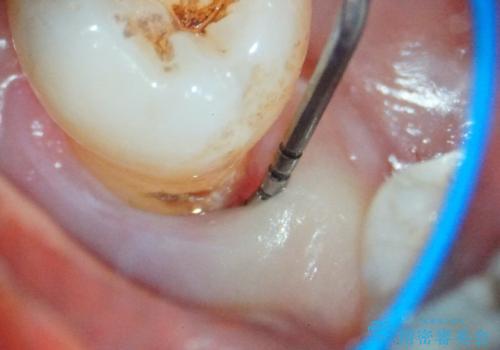

右下小臼歯は歯周病で大きな骨欠損を認めていました。

できる限り歯が保存できるように治療したいとのことでエムドゲインを用いた再生治療を行っています。

歯周病の原因に咬合干渉が疑われる為、ワイヤーにて固定を行っています。

- 外科手術のため、術後に痛みや腫れ、違和感を伴います

- 歯周組織再生治療は患者様の状態によって術後の経過が異なります(見た目が改善しない場合もあります)